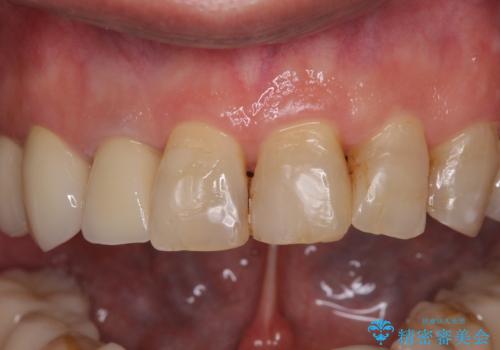

- 前歯のデコボコや、奥歯を咬んだときに痛みがあるとのことで来院された患者様です。

全体的に問題が多く、全てをしっかりと治療したいとのことでした。

全体的に中等度の歯周病と診断されたため、歯周外科処置やインプラントによる咬合回復から進めて行き、矯正治療による歯列改善を行った後にオールセラミッククラウンにて補綴することとしました。

矯正治療を希望して来院されましたが、歯周病を併発していたため、矯正治療開始前の処置が非常に多くなりました。特に歯槽骨の再生治療を行ったため、外科処置後の静置期間が長くなり、4年弱の治療期間となりました。

治療後には咬みやすさだけでなく、前歯が大変審美的に仕上がり、患者様には大変満足していただきました。